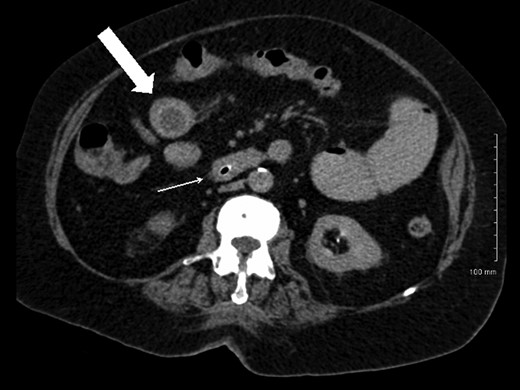

A plain abdominal radiograph was also unrevealing. She proceeded to have computerized tomography (CT) scan of her abdomen and pelvis, which showed dilated small bowel loops consistent with small bowel obstruction. There were two filling defects noted, one in her proximal ileum suspicious for a non-calcified gallstone and the second distally in her terminal ileum (Figs 1 and 2). Appearances were suggestive of gallstone ileus. She was adequately resuscitated and underwent a laparotomy. The small bowel was narrowed in two segments: proximally secondary to an impacted gallstone and an area of stricturing noted distally. Both segments were resected with end-to-end anastomosis performed in a two-layer standard hand-sewn fashion. The clinical impression was one of dual pathology including Crohn's disease and gallstone ileus. She did not undergo a cholecystectomy or repair of her cholecystoduodenal fistula. She made an uneventful post-operative recovery and was discharged home well on Day 7.

Coronal CT image demonstrating gallstone ileus (block arrow) and stricture in distal ileum (thin arrow).